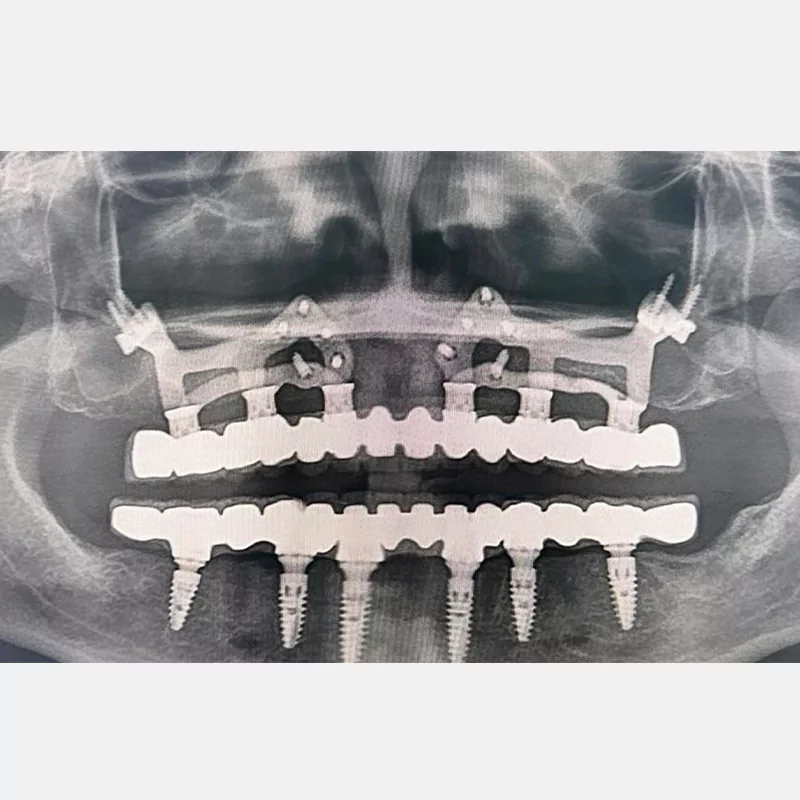

Modern diş hekimliğinde, çene gelişimini tamamlamamış veya ciddi kemik kaybı yaşayan hastalar için kişiye özel titanyum implantlar ile çözüm bulunmaktadır. CAD/CAM teknolojisi ve lazer sinterleme yöntemiyle üretilen bu implantlar, hastanın bireysel anatomik yapısına tam uyum sağlayarak geleneksel implantların uygulanamadığı vakalarda mükemmel bir alternatif oluşturmaktadır. Özellikle ileri derecede kemik kaybı olan hastalar için geliştirilen subperiosteal implantlar, periostun altına yerleştirilerek minimal invaziv bir yaklaşım sunarken, bilgisayarlı tomografi verileri ve sonlu eleman analizleriyle optimize edilmiş tasarımları sayesinde hem estetik hem de fonksiyonel sonuçlar garanti etmektedir. Bu yenilikçi teknoloji, tek seansta implant ve protez uygulamasına imkan vererek hastaların aynı gün doğal gülüşlerine kavuşmalarını sağlarken, kemik greftleme gibi ek işlem ihtiyacını ortadan kaldırarak cerrahi süreci büyük ölçüde kolaylaştırmaktadır. Kişiye özel tasarımı ve üstün biyouyumluluğu sayesinde, daha önce tedavisi mümkün görülmeyen kompleks vakalarda bile başarılı sonuçlar sunan bu implantlar, modern diş hekimliğinde yeni bir çağ açarak hastaların yaşam kalitesini artırmayı hedeflemektedir.

Hekim tarafından onaylanan Custiplate, 3 boyutlu yazıcı teknolojisi kullanılarak Grade 23 (Ti6Al4V) Medikal Titanyum Alaşımından üretilir. - KARGO

VAKA 1

VAKA 2

VAKA 3

VAKA 4